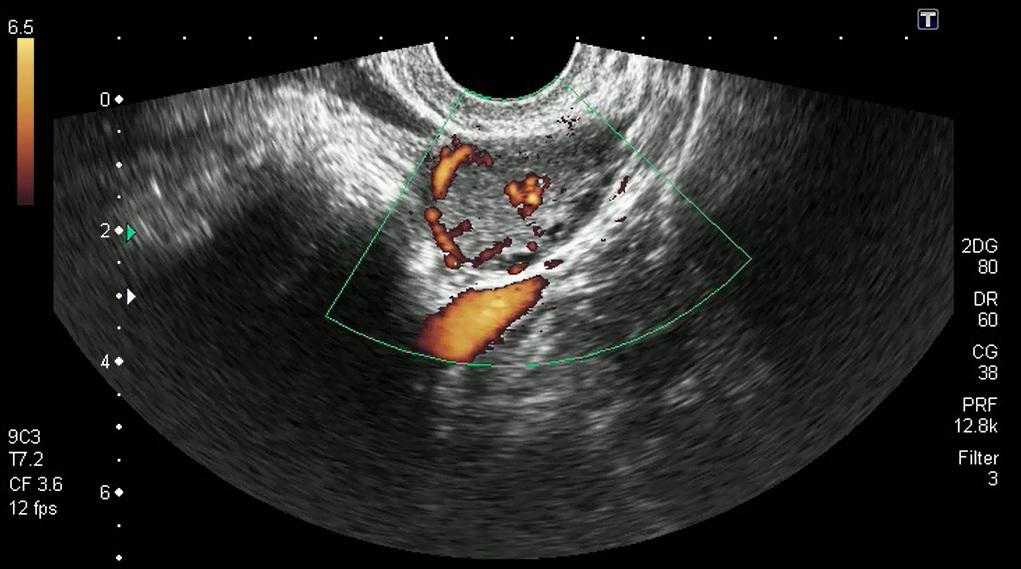

Аппарат УЗИ показывает ЖТ округлым неоднородным образованием. Оно просматривается и когда проводится трансабдоминальное УЗИ, через стенки брюшины. Однако наиболее достоверные результаты получаются на трансвагинальном УЗИ, когда используется внутривагинальный датчик.

На УЗИ недостаточность ЖТ диагностируется по несоответствию его параметров, когда тело железы не достигает 10 мм. Диагностика уточняется исследованием крови в лабораторных условиях, когда проверяется содержание прогестерона. При этом на УЗИ постоянно проверяется наличие желтого тела в яичнике, и объясняется пациентке, что это такое, какое значение оно имеет для развития нормальной беременности.

Киста ЖТ диагностируется на УЗИ тоже по его параметрам. Когда железа вырастает больше нормальных размеров, выше 30 мм, устанавливается диагноз: киста.

В такой ситуации железа полноценно выполняет свои функции, продуцирует необходимый прогестерон. И беременность, несмотря на наличие кисты, обычно развивается в пределах нормы. Киста железы не вредит организму, потому что исчезает одновременно с перерождением ЖТ. Но при ее росте необходимо постоянное наблюдение лечащего врача.